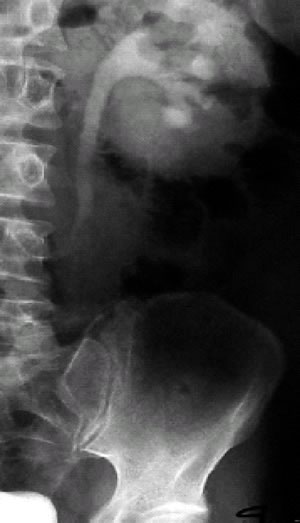

Figura 4: urografia intravenosa; idronefrosi sx. con evidenza di stenosi ureterale all'altezza di L-4.(Da referenza 30)